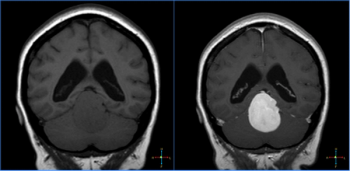

In a young patient with chronic seizures, what is the diagnosis?